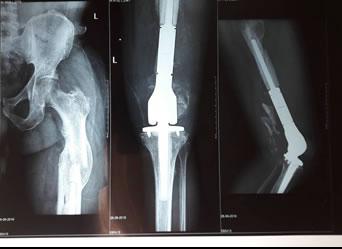

Proximal femoral endoprosthetic replacement | total knee replacement | total hip replacement| distal femoral endoprosthetic replacement

Distal Femoral Endoprosthetic Replacement

xray of a successful Total Knee Replacement